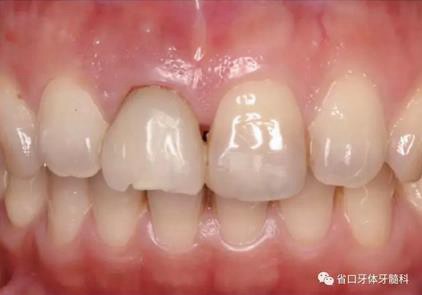

圖1 術(shù)前口內(nèi)照

圖2 術(shù)前口內(nèi)照

圖3 術(shù)前口內(nèi)照

1.?病例簡(jiǎn)介 43歲女性患者,主拆:右上前牙松動(dòng)不適數(shù)日要求修復(fù)。現(xiàn)病史:患者數(shù)年前右上前牙因“齲壞”于外院行根管治療(具體不詳),數(shù)日前牙冠松動(dòng)不適,現(xiàn)覺(jué)影響咀嚼及美觀,遂來(lái)我院要求進(jìn)一步診治。否認(rèn)高血壓、心臟病等重大疾病,否認(rèn)結(jié)核、肝炎等傳染病史,否認(rèn)手 術(shù)、輸血史等,未發(fā)現(xiàn)藥物過(guò)敏。無(wú)吸煙習(xí)慣。臨床檢查:口外觀顏面基 本對(duì)稱,皮膚無(wú)紅腫破潰,顳下頜關(guān)節(jié)區(qū)無(wú)彈響、雜音、壓痛,開(kāi)口度約 37mm,開(kāi)口型“↓”,頜下、刻下和頸部未及腫大淋巴結(jié)。中位笑線??趦?nèi)檢查,口腔衛(wèi)生可,色素(+),BOP(-),PD=2mm,上頜右側(cè)中切 牙冠部變色,冠根折斷至齦下3mm,叩不適,松動(dòng)Ⅱ°~Ⅲ°。牙齦稍紅, 齦緣水平及齦乳頭高度可,屬于中厚齦生物型,附著齦寬度約5mm,唇系帶附著可。上頜右側(cè)中切牙缺牙間隙與對(duì)側(cè)同名牙一致,約>7mm,修復(fù)空 間良好。與對(duì)頜牙覆合覆蓋正常。MCT檢查示上頜右側(cè)中切牙冠根折斷至骨 下,根管內(nèi)見(jiàn)充填物,根充不全,根尖見(jiàn)陰影,大小約3mm×3mm。牙槽窩根方可用骨量可,唇側(cè)骨壁完整,冠方骨壁厚度約1mm。

(4)最終修復(fù)與隨訪:經(jīng)過(guò)3個(gè)月左右的塑形,上頜右側(cè)中切牙臨時(shí)修復(fù)固位良好,菌斑控制良好,近遠(yuǎn)中齦乳頭充盈良好,齦緣水平及形態(tài)與 鄰牙相對(duì)稱。牙齦塑形穩(wěn)定后,以臨時(shí)修復(fù)體制作個(gè)性化轉(zhuǎn)移桿并取模轉(zhuǎn)移,并以原廠氧化鋯基臺(tái)制備個(gè)性化基臺(tái)及全瓷冠。正確就位最終基臺(tái),加 力30N·cm。制備粘接代型,去除多余粘接劑,以Unicem粘接固位上頜右側(cè)中切牙全瓷修復(fù)體。固化穩(wěn)定后,再次確定咬合無(wú)干擾。最終修復(fù)完成后 隨訪3個(gè)月及6個(gè)月,上頜右側(cè)中切牙種植修復(fù)固位穩(wěn)定,近遠(yuǎn)中齦乳頭充 盈良好,唇側(cè)齦緣水平穩(wěn)定。

上頜右側(cè)中切牙修復(fù)體固位良好,牙齦乳頭充盈良好,齦緣水平對(duì)稱 修復(fù)體與對(duì)側(cè)同名牙協(xié)調(diào)一致。外觀笑容美觀協(xié)調(diào)?;颊邼M意。X線檢查示 上頜右側(cè)中切牙種植體周穩(wěn)定骨質(zhì)包繞,唇側(cè)骨板>2mm,相鄰牙槽骨高度穩(wěn)定,基臺(tái)及修復(fù)體就位良好。分別根據(jù)Furhauser的PES和Bulser的WES 進(jìn)行美學(xué)評(píng)分,總分值為20,美學(xué)效果良好。